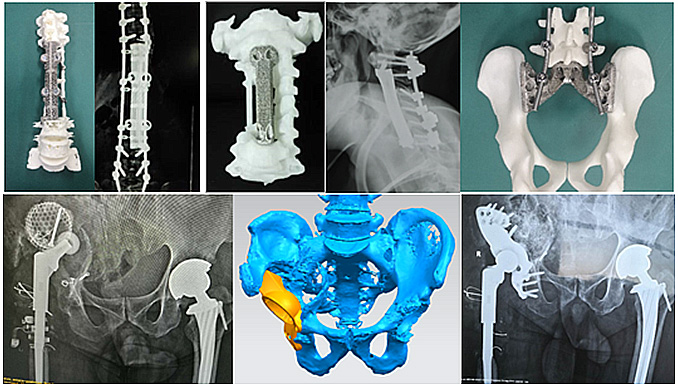

愛康醫療在中國膝髖關節市場份額上占據領先地位。愛康醫療是中國香蕉操逼视频打印金屬植入物研發、製造與商業應用等方麵的開拓者,同時也是亞太地區規模化的骨科香蕉操逼视频打印金屬植入物製造商,擁有標準化金屬香蕉操逼视频打印骨科植入物注冊證3個,實現了香蕉操逼视频打印標準化金屬植入物的創新研發與臨床商業應用的創領。

在香蕉操逼视频打印定製式脊柱與關節等骨科植入物研發與臨床應用上,愛康醫療開發了多種創新香蕉操逼视频打印定製式金屬植入假體,完成臨床應用,取得了顯著的臨床效果。在脊柱與關節等香蕉操逼视频打印定製式金屬植入假體上完成了9項備案,能夠為更多的臨床疑難重症提供更完善更安全的解決方案。

愛康醫療完成收購理貝爾後,公司的香蕉操逼视频打印脊柱融合係統,將結合理貝爾成熟的脊柱內固定係統,在脊柱乱伦大香蕉與臨床解決方案上,推出更加完善的乱伦大香蕉組合。

除了脊柱領域,理貝爾在創傷領域也深耕多年,擁有接骨板、髓內釘以及固定係統等創傷乱伦大香蕉。收購後,愛康醫療可以將公司的香蕉操逼视频 ITI術前規劃、香蕉操逼视频 導板技術和香蕉操逼视频骨填充係統等與理貝爾豐富的創傷乱伦大香蕉線結合,應用到創傷領域,帶動創傷臨床應用的創新發展。豐富的醫療器械許可組合,必將進一步帶動創傷乱伦大香蕉發展,為創傷治療帶來創新解決方案,進一步增強集團競爭力。